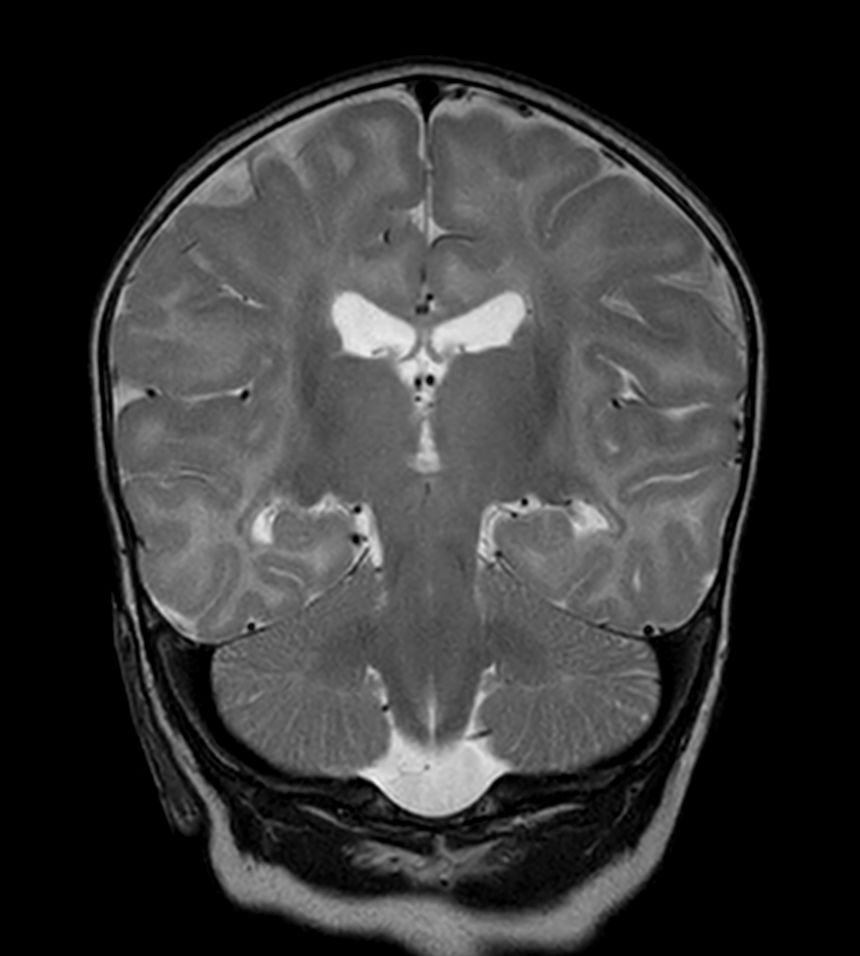

Coronal T2w TSE with ComforTone